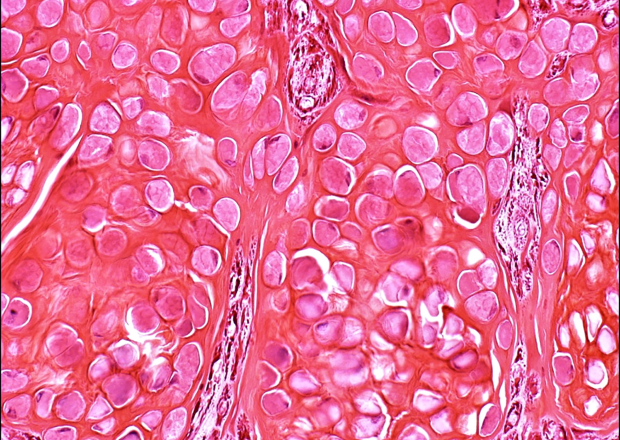

Dr Carmen van Dooijeweert’s PhD thesis is a great example of how a large collection of archived pathology records can be used for research. Van Dooijeweert’s research, which focused on improving the assessment of biomarkers for breast cancer, was largely based on protocolised pathology reports from the national Palga database.